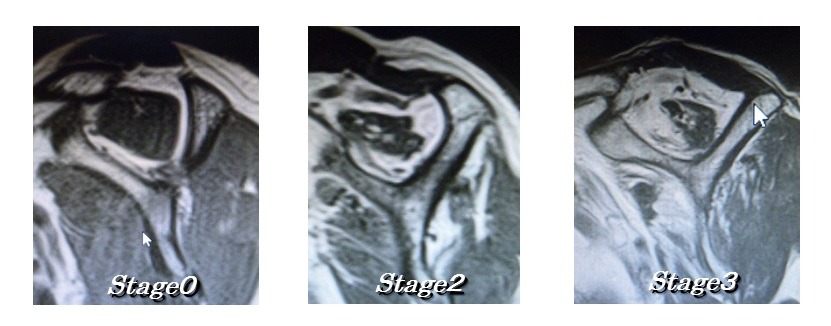

Goutallier分類(棘上筋の脂肪変性の程度)

| Stage0 | 脂肪変性なし |

| Stage1 | わずかに脂肪変性 |

| Stage2 | 筋肉成分>脂肪成分 |

| Stage3 | 筋肉成分=脂肪成分 |

| Stage4 | 筋肉成分<脂肪成分 |

Stage0~2までは腱板再建を考慮し、Stage3と4は再建しても成績悪く再断裂がおきやすいとの報告もあります。